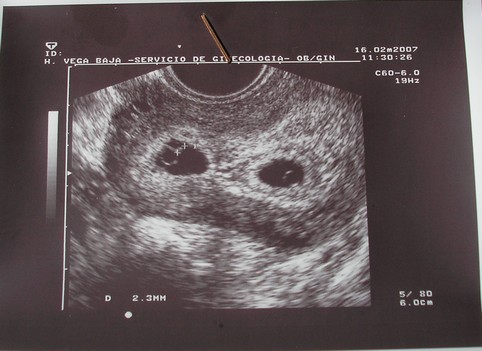

A babak nonek, vagyis az egyikben latszik embrio es dobog a szivecskeje a masikban nem de az is nott, szoval ugy nez ki fejlodnek mindketten (lekopogom) jovo het szerdan kell visszamennem.